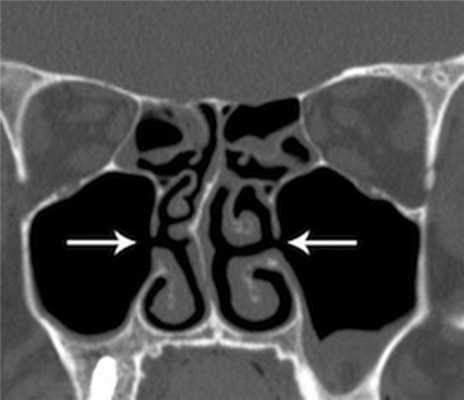

(Слева) На корональной КЛКТ (реконструкция) визуализируется добавочное переднее устье.

(Справа) На корональной КЛКТ визуализируются добавочные устья В, расположенные за основными. Картина сопоставима с таковой после хирургического вмешательства по поводу хронического синусита. Определяется утолщение слизистой оболочки В обеих верхнечелюстных пазух, обусловленное хроническим воспалением.